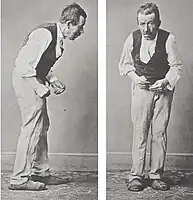

Bradykinesia describes difficulties in motor planning, beginning, and executing, resulting in overall slowed movement with reduced amplitude that affects sequential and simultaneous tasks.[22] Bradykinesia can also lead to hypomimia, reduced facial expressions.[21] Rigidity, also called rigor, refers to a feeling of stiffness and resistance to passive stretching of muscles that occurs in up to 89 percent of cases.[23][24] Postural instability typically appears in later stages, leading to impaired balance and falls.[25] Postural instability also leads to a forward stooping posture.[26]

Beyond the cardinal four, other motor deficits, termed secondary motor symptoms, commonly occur.[27] Notably, gait disturbances result in the Parkinsonian gait, which includes shuffling and paroxysmal deficits, where a normal gait is interrupted by rapid footsteps—known as festination—or sudden stops, impairing balance and causing falls.[28][29] Most PD patients experience speech problems, including stuttering, hypophonic, "soft" speech, slurring, and festinating speech (rapid and poorly intelligible).[30] Handwriting is commonly altered in Parkinson's, decreasing in size—known as micrographia—and becoming jagged and sharply fluctuating.[31] Grip and dexterity are also impaired.[32]

In 1817, English physician James Parkinson published the first full medical description of the disease as a neurological syndrome in his monograph An Essay on the Shaking Palsy.[244][245] He presented six clinical cases, including three he had observed on the streets near Hoxton Square in London.[246] Parkinson described three cardinal symptoms: tremor, postural instability and "paralysis" (undistinguished from rigidity or bradykinesia), and speculated that the disease was caused by trauma to the spinal cord.[247][248]